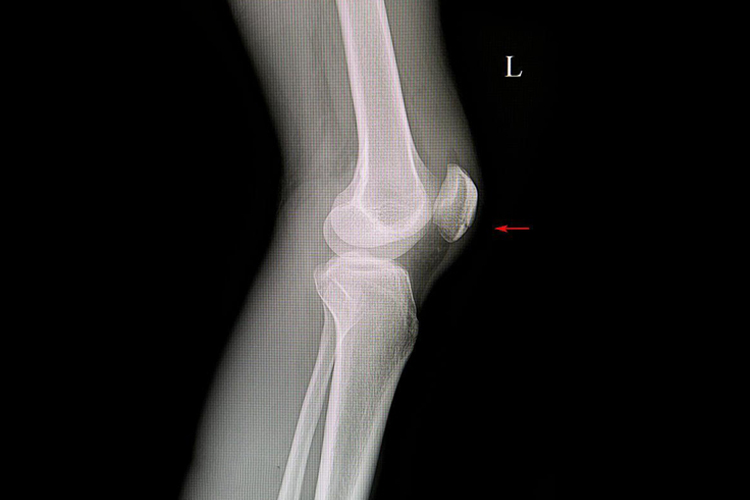

膝盖肌腱炎最常见的临床症状为疼痛。在髌腱与胫骨结节之间的任何位置都可发生。疼痛在活动或运动开始时尤其明显,而后发展到影响运动,或发展到影响日常生活的动作,如爬楼梯或从椅子上起立时。体格检查时发现膝部前方压痛明显,有时膝不能完全伸直或伸膝力量减弱或伸膝时有不平滑感。X线检查并不显示腱内病变,但可发现有骨赘、钙化等表现。